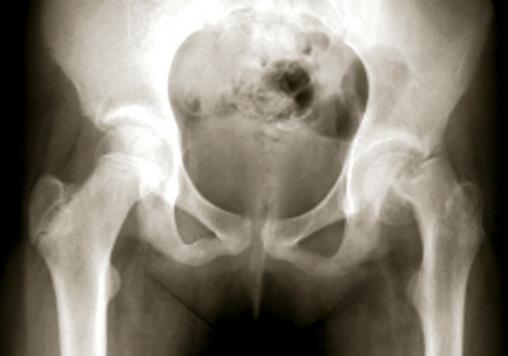

L'épiphyse a basculé complétement et s'est détachée du col fémoral.Le tableau est alors celui d'une impotence complète du membre inférieur.